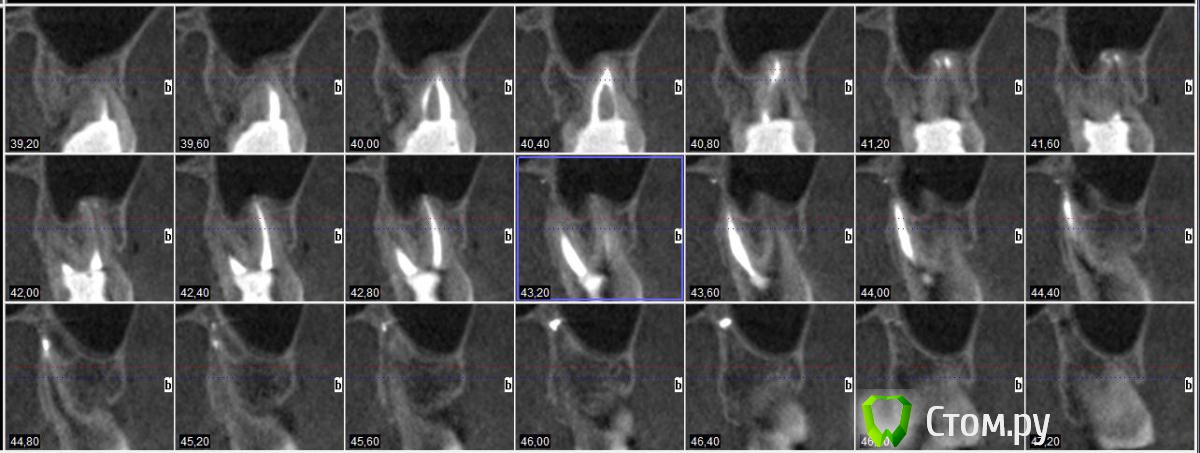

winnt Опубликовано 18 июля, 2014 Автор Поделиться Опубликовано 18 июля, 2014 То есть 7ой зуб чувствует холод? Болит меньше когда прикладываете? А скололся скорее всего из-за кариеса, антогонист скол не вызовет, либо стираемость может быть и увеличение чувствительности. Пломбу вам случаем не завысили?Холод чувствует, но как-то тупее чем здоровый зуб и боль остается дольше после холодного;Когда прикладываю болит больше и после того как убираю боль "остается" дольше чем в здоровом;Скололся от удара нижней челюстью об торпеду авто;Пломбу не завысили, это точно. Покрутил в КТ этот зуб и стало чуть страшно будто от корня этого зуба "что-то растет" прямо в НЧ.канал: Ссылка на комментарий

Гарриевич Опубликовано 18 июля, 2014 Поделиться Опубликовано 18 июля, 2014 на последнем снимке остеит, то есть хронические периапикальные изменения есть. скорее всего травма вызвала ответную реакцию пульпы зуба и ее частичное поражение. желательна конечно очная консультация 1 Ссылка на комментарий

winnt Опубликовано 18 июля, 2014 Автор Поделиться Опубликовано 18 июля, 2014 на последнем снимке остеит, то есть хронические периапикальные изменения есть. скорее всего травма вызвала ответную реакцию пульпы зуба и ее частичное поражение. желательна конечно очная консультация Спасибо Гарриевич, нашел описание в сети, все сходиться: condensing osteitis( focal sclerosing osteomyelitis) даже пишут, что чаще всего встречается на молярах НЧ.Вот только вопрос не может ли остеит в моем случае "вырасти в канал", или он распространяется только по структуре кости и скорей всего обойдет канал вокруг чем попадет внутрь? Как вы думаете есть показания к эндо в моем случае, наверное если не беспокоит зуб то с такой проблемой можно его не трогать, но в моем случае он "достает" меня очень долго и это похоже на что-то хроническое? Winnt, вашу бы энергию, да в мирное бы русло. Сходите к другому врачу, пусть пробу эндофростом проведет, и ЭОД. Эндофростом делали пробу - реакция есть, боль уходила довольно быстро, я и сам пробовал только вместо спец баллончика, брал для заправки зажигалок.Вот насчет ЭОД звонил пару врачам говорят нет, поищу еще, если не найду то куплю себе китайский.red_butler может быть такое что термо пробы не могут показать например хронический пульпит, другие изменения в переапикальной области. когда уже в пульпе пошли необратимые изменения и нужно эндо, а ЭОД покажет? Ссылка на комментарий